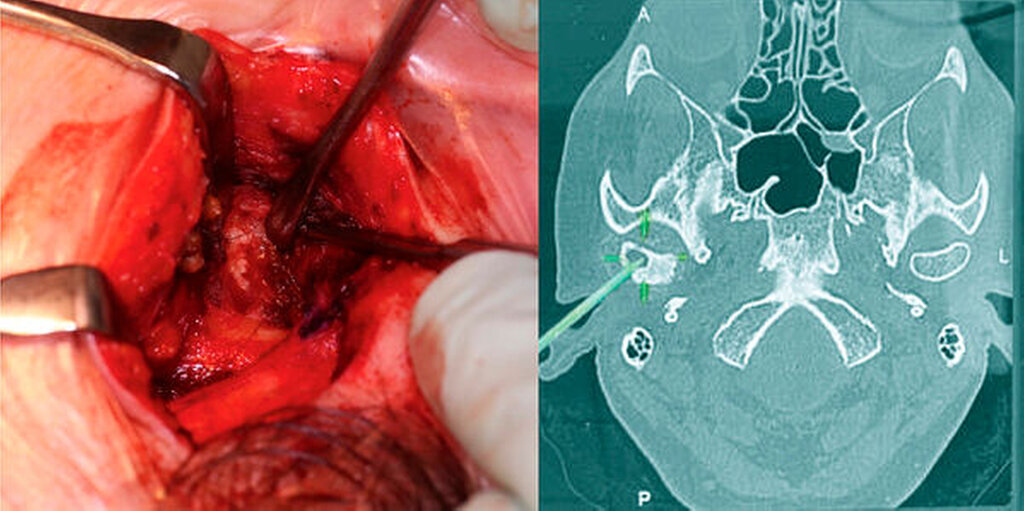

Zur genaueren Eingrenzung und Beurteilung der Knochenstrukturen wurde allerdings eine zusätzliche CT-Untersuchung empfohlen, die im Hinblick auf eine navigationsgestützte Probenentnahme nach kranialem Einbringen von vier Markierungsschrauben durchgeführt wurde. Hierbei wiederum ergab sich in Korrelation mit der bereits durchgeführten MRT-Untersuchung eine Mehrsklerosierung des Capitulums rechts mit geringen Arrosionen im apikalen Anteil und einer glatt begrenzten Zyste. Somit wurde von den radiologischen Kollegen die Verdachtsdiagnose eines Chondrosarkoms aufgestellt (Abbildung 2).

In der navigationsgestützten Probenentnahme in der darauffolgenden Woche präsentierten sich der perikapituläre Kapselapparat als solide kalzifiziert und verdickt sowie der Inhalt des Zystenkavums und die das Kiefergelenk umgebende Raumforderung – die soweit möglich entfernt wurde – als gallertartige Masse mit kleinen, kristallartigen Kalzifikationen (Abbildung 3). Die histopathologische Befundung zeigte die Charakteristika einer Kristallarthropathie mit assoziierter Fremdkörper- und Entzündungsreaktion, passend zu einer Kalziumpyrophosphat- Arthropathie (Abbildung 4). Nach unauffälligem postoperativem Verlauf konnte die Patientin entlassen werden. Im Rahmen der klinischen Untersuchung nach zwei Wochen unter Therapie mit einem nichtsteroidalen Antirheumatikum (NSAR) war sie bei vollständig regredienter Schwellung beschwerdefrei.